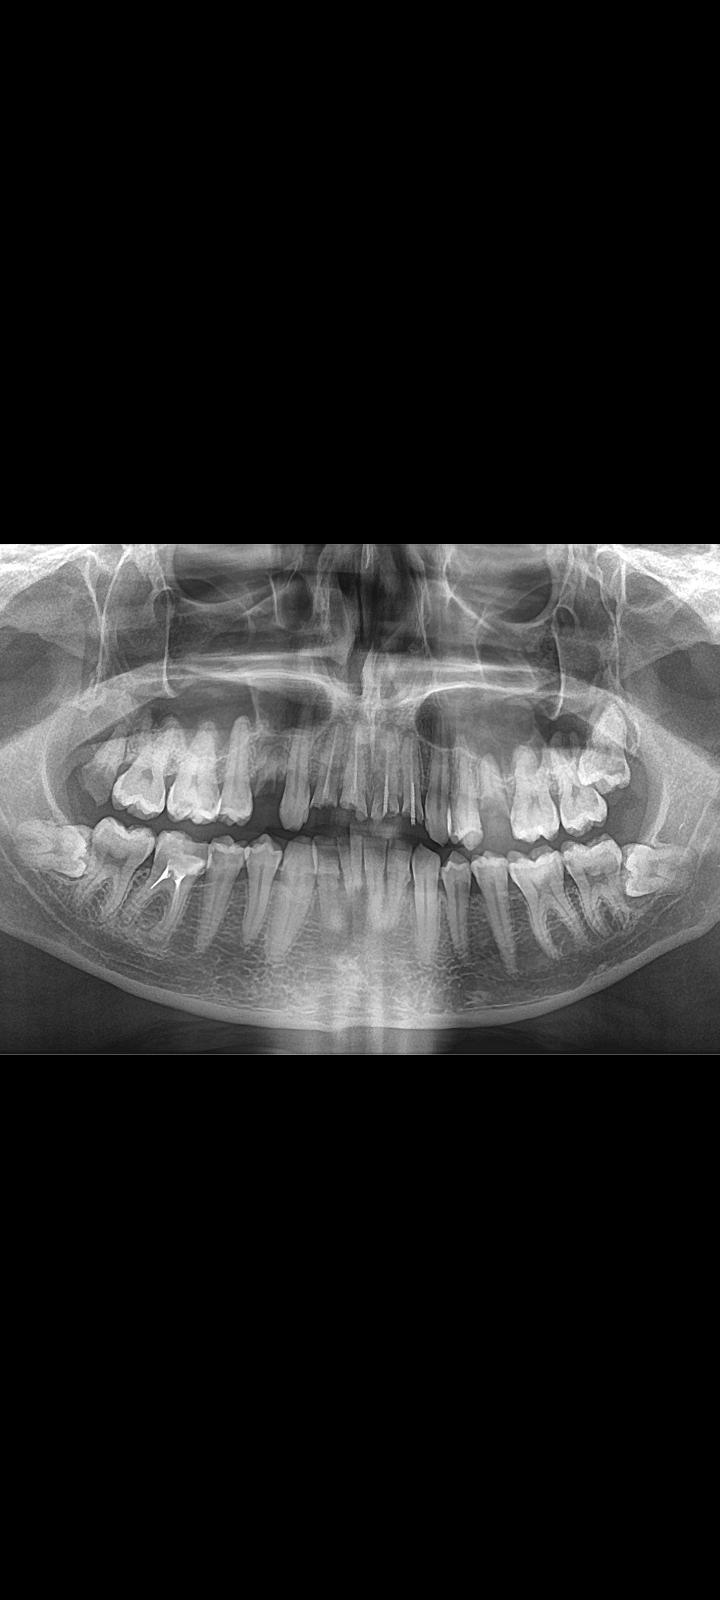

Аноним 08/08/25 Птн 06:11:54 1635233 32

1759678455236.jpg 1558Кб, 2536x3256

2536x3256

1759678455268.jpg 1853Кб, 2252x3434

2252x3434

1759678455308.jpg 217Кб, 1056x1126

1056x1126

1000076562.jpg 534Кб, 1920x1440

1920x1440

1759678455314.jpg 479Кб, 1920x1440

1759678455331.jpg 508Кб, 1920x1440

1759678455339.jpg 562Кб, 1920x1440

Насколько все плохо? Сколько готовить?

Живу в Москве, боюсь. Так что придется искать тех, кто с наркозом работает.